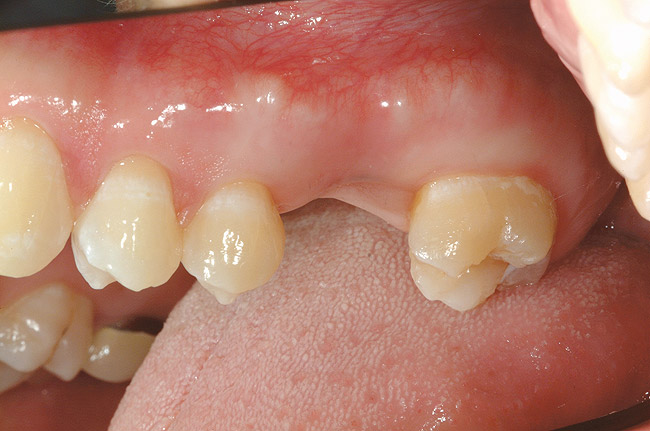

Restoration of partially edentulous patients with dental implants has not only added a new opportunity for replacement of missing teeth but also presented a different set of challenges for providing successful, long-term dental prostheses. Initially, many treatment protocols that were followed for the completely edentulous patient proved to be less than ideal for the partially edentulous patient.15 Combining natural teeth and dental implants in the same arch, sometimes in the same quadrant, creates a biomechanical difference between teeth and implant(s) during function. Traditional three-unit fixed partial dentures placed on two dental implants can be successful. Yet when forces of occlusion are high, the need to place one implant per tooth or three implants to support four units in the posterior quadrants is often recommended.8,15 Moreover, blending natural teeth and bony/gingival contours with the edentulous spaces being restored with implants can be difficult in meeting the patient’s expectations and can potentially create difficulty with oral hygiene access.

Single-tooth replacement with dental implants has proven to be very beneficial yet challenging for both the patient and treating dentist. Long-term success has now been achieved in the anterior and posterior areas,16 although specific characteristics can affect the prognosis, such as the quality and quantity of bone, occlusal loads, and parafunctional habits. While these restorations have been shown to be highly successful, there remains the critical challenge of completely restoring the esthetic and functional needs for the patient and making these restorations undetectable from the other natural teeth. A complete understanding of the edentulous space is necessary for an accurate diagnosis, which then allows for the development of a treatment sequence for the best possible outcome. Frequently, preprosthetic procedures are required prior to implant placement if a compromise is to be avoided. Consideration should be given not only to the esthetic value of the single-implant tooth replacement but also should account for the patient’s oral hygiene needs.